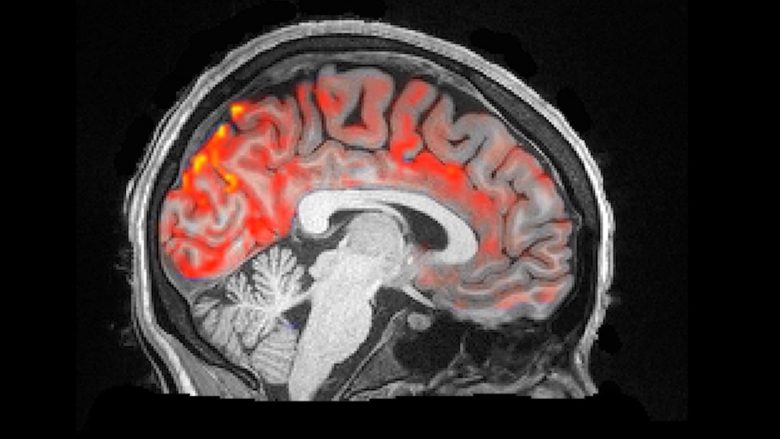

Neuro-shkencëtarët kanë bërë xhirim të mrekullueshëm në të cilin shihet pastrimi pulsues i aparatit tonë të trurit, shkruan Science Alert.

Sipas hulumtimit më të ri, gjatë natës nëpër trurin tonë rrjedhin valët e lëngut cerebrospinalë, duke pulsuar ritmikisht derisa ne flemë gjumë dhe eliminojnë toksinën e dëmshme.